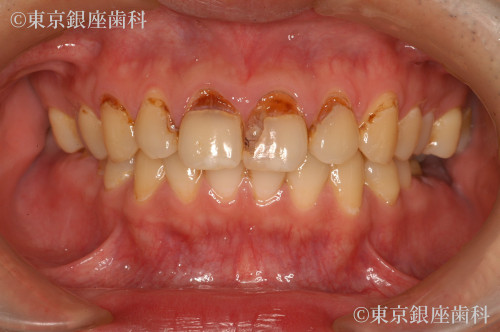

ひどい虫歯で歯がボロボロ

After

インプラント及びセラミック処置を実施

術後、嚙み心地に違和感が発生する可能性がある